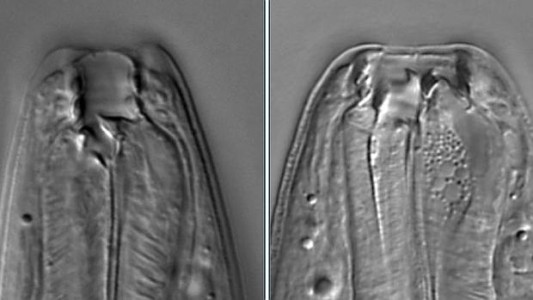

Descubren un gusano que puede tener cinco caras distintas